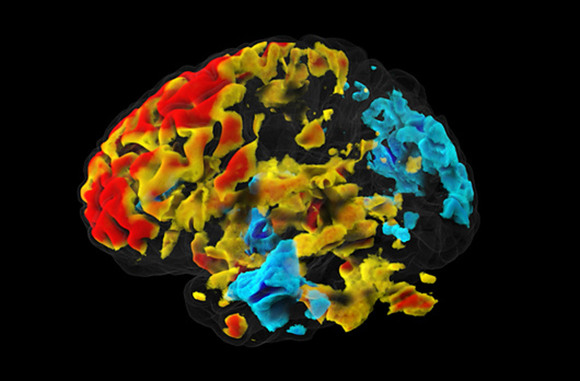

لكل ڤوكسل، نود أن نفحص ما إذا كان هناك تغيير في الإشارة أثناء تنفيذ المهمة، مقارنة بمستوى الإشارة المقاس في ظروف المجموعة الضابطة. دماغ مع وحدات ڤوكسل تزيد من نشاطها (بألوان دافئة) وأخرى تقلّل من نشاطها (بألوان باردة) عندما تماهى المشاركون في التّجربة مع مشاعر الآخرين | الصّورة مقدّمة من د. عدي يانيف